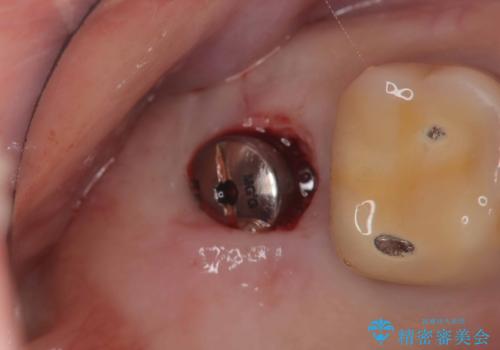

根尖性歯周炎|歯根嚢胞|インプラント治療

- 右上7番に瘻孔を認め、根管治療を実施しましたが、瘻孔が再発し治癒が得られなかったため、抜歯のうえインプラントによる補綴治療を行いました。

抜歯と歯根嚢胞の除去を行った後、インプラントで治療しました。治療後は「自分の歯のように咬める」と大変ご満足いただけました。